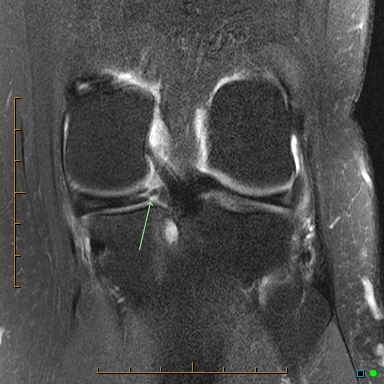

Meniscal root tear

Tear at the junction of the posterior horn medial meniscus and its attachment of the tibial eminence. This is known as the meniscal root.

Case Discussion

These tears are unusual and occur either as an acute injury in young patients or as a degenerative process in older patients. As the meniscus is reasonably well vascularised at the root, surgical repair is recommended in younger patients. In older patients with degeneration there is often associated chondral damage thus repair is more problematic and can fail.

Meniscal root tears are a type of meniscal tear in the knee where the tear extends to either the anterior or posterior meniscal root attachment to the central tibial plateau. They often tend to be radial tears extending into the meniscal root.

Radiographic features

MRI

Best assessed on T2 weighted sequences. When it involves the posterior root, medial root tears are easier to diagnose than lateral root tears.

On medial posterior root tears there is often 2:

shortening or absence of the root on sagittal images

vertical fluid cleft on coronal fluid-sensitive (T2) images

On posterior root radial tears of the lateral meniscus, the appearance may be similar to radial tears in other locations.

For root tears in general, sagittal imaging may demonstrate a meniscal ghost sign.

Other features include:

truncation sign on coronal images 4

features meniscal extrusion on coronal plane 4